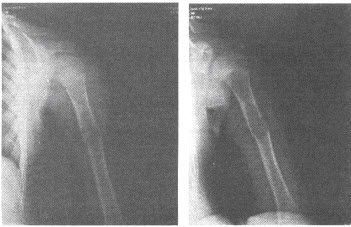

36、单项选择题

男,28岁,摔伤后肩部疼痛,活动受限,结合影像学表现,最可能的诊断是()

A.柯莱斯骨折

B.肱骨头骨折

C.肱骨外科颈骨折

D.加莱阿齐骨折

E.蒙泰贾骨折